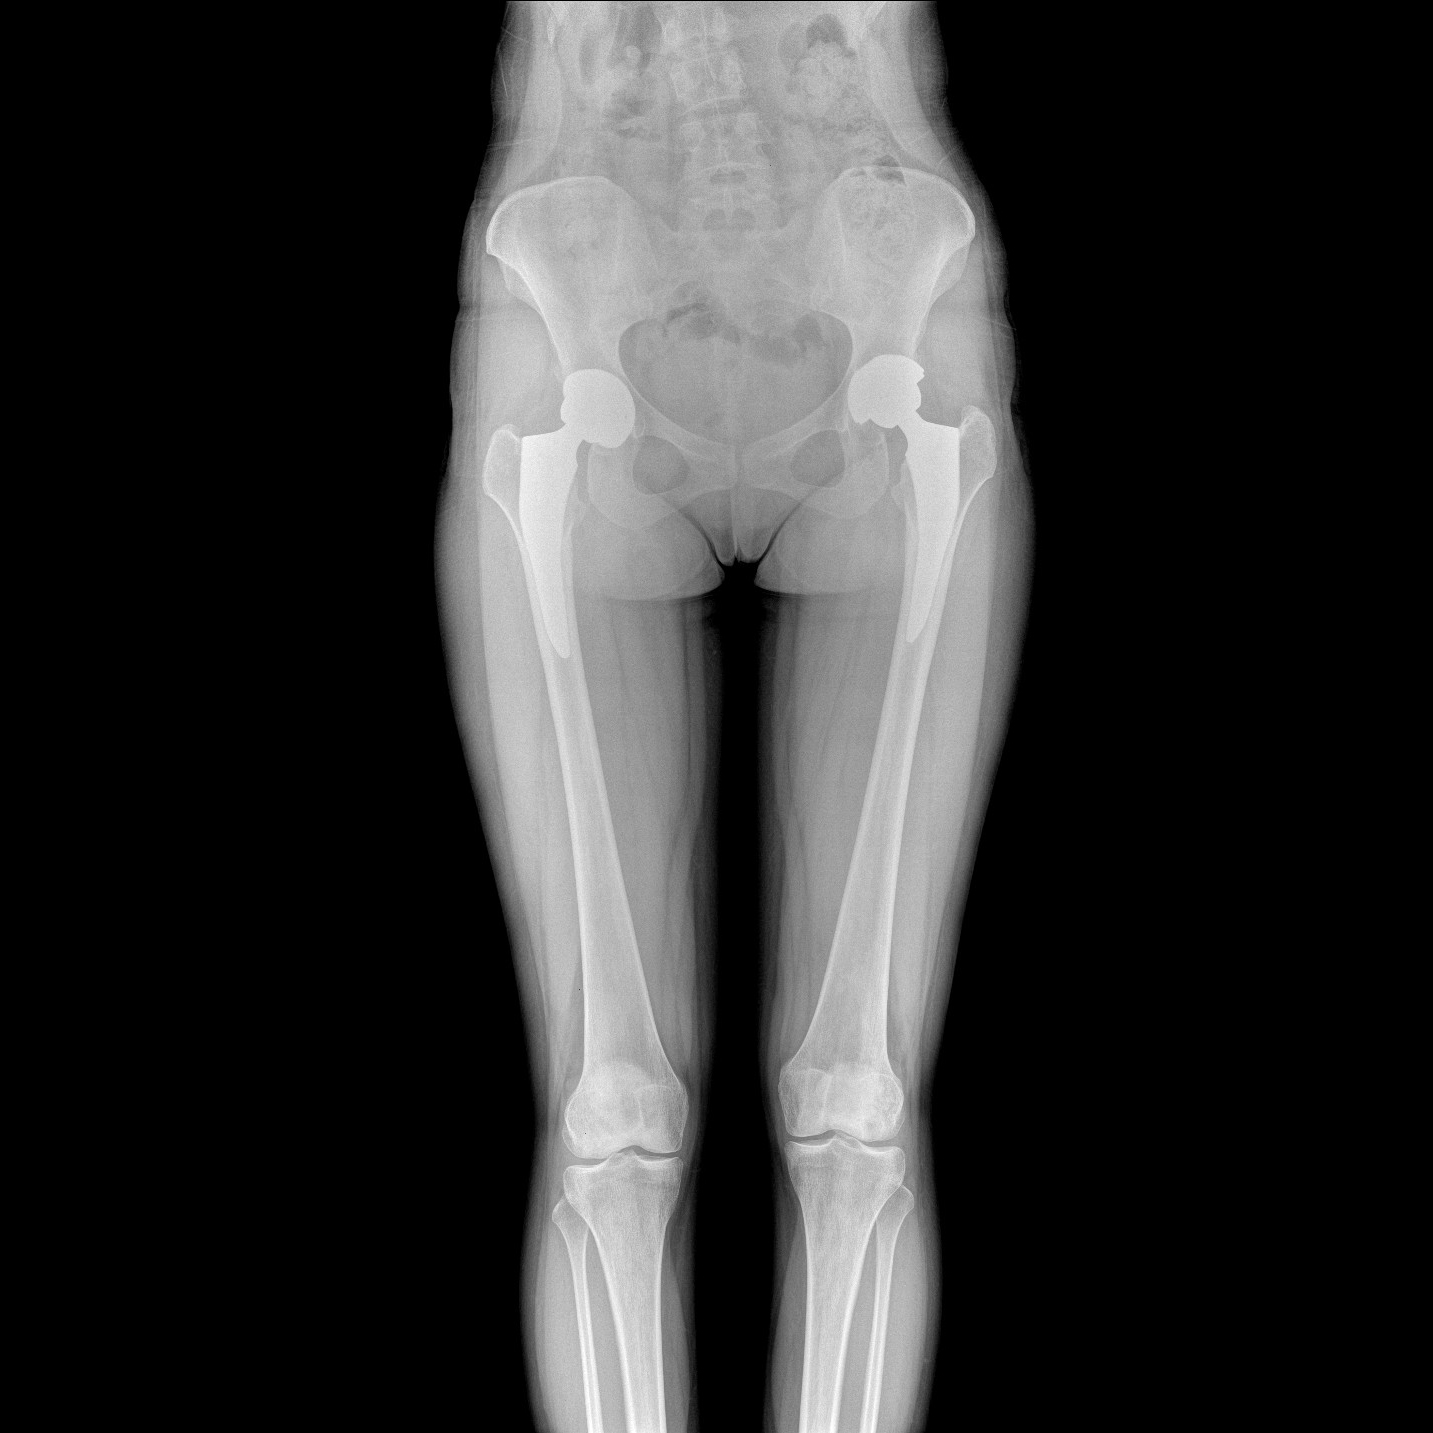

17"*34"有效視野,一次成像不拼接。相較于多張攝影再軟件拼接的DR設備,PLX8600解決了拼接圖像存在密度不均勻,拼接處圖像配準和放大效應等問題,給臨床帶來了大視野影像解決方案,可一次性覆蓋全脊柱或雙下肢影像。